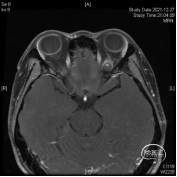

头颅MR体检偶然发现左侧眶尖占位,初步诊断海绵状血管瘤,查体无明显阳性体征。

该部位的手术可选多种入路,经眉弓锁孔、经额、经眶外侧壁等,然而施炜、陈建内镜团队选择了临床较少使用的经眶入路!创伤小且对患者的容貌影响小,术前团队进行了相关解剖研究!

研究表明此入路除细小的滋养血管外无其他重要结构!皮肤切口选择近眶缘眉弓美容切口,紧贴眶上壁分离骨膜,保护眶筋膜,病变紧贴眶上壁,导航下确定眶尖紧贴眶上壁的病变,外观呈浅紫兰色,考虑既往有出血所致,显露肿瘤!

磨除局部少许隆起的骨嵴以增加操作空间,切开眶骨膜分离并完整切除病变,术中证实为海绵状血管瘤,直径约1厘米,手术全程在内镜下完成。